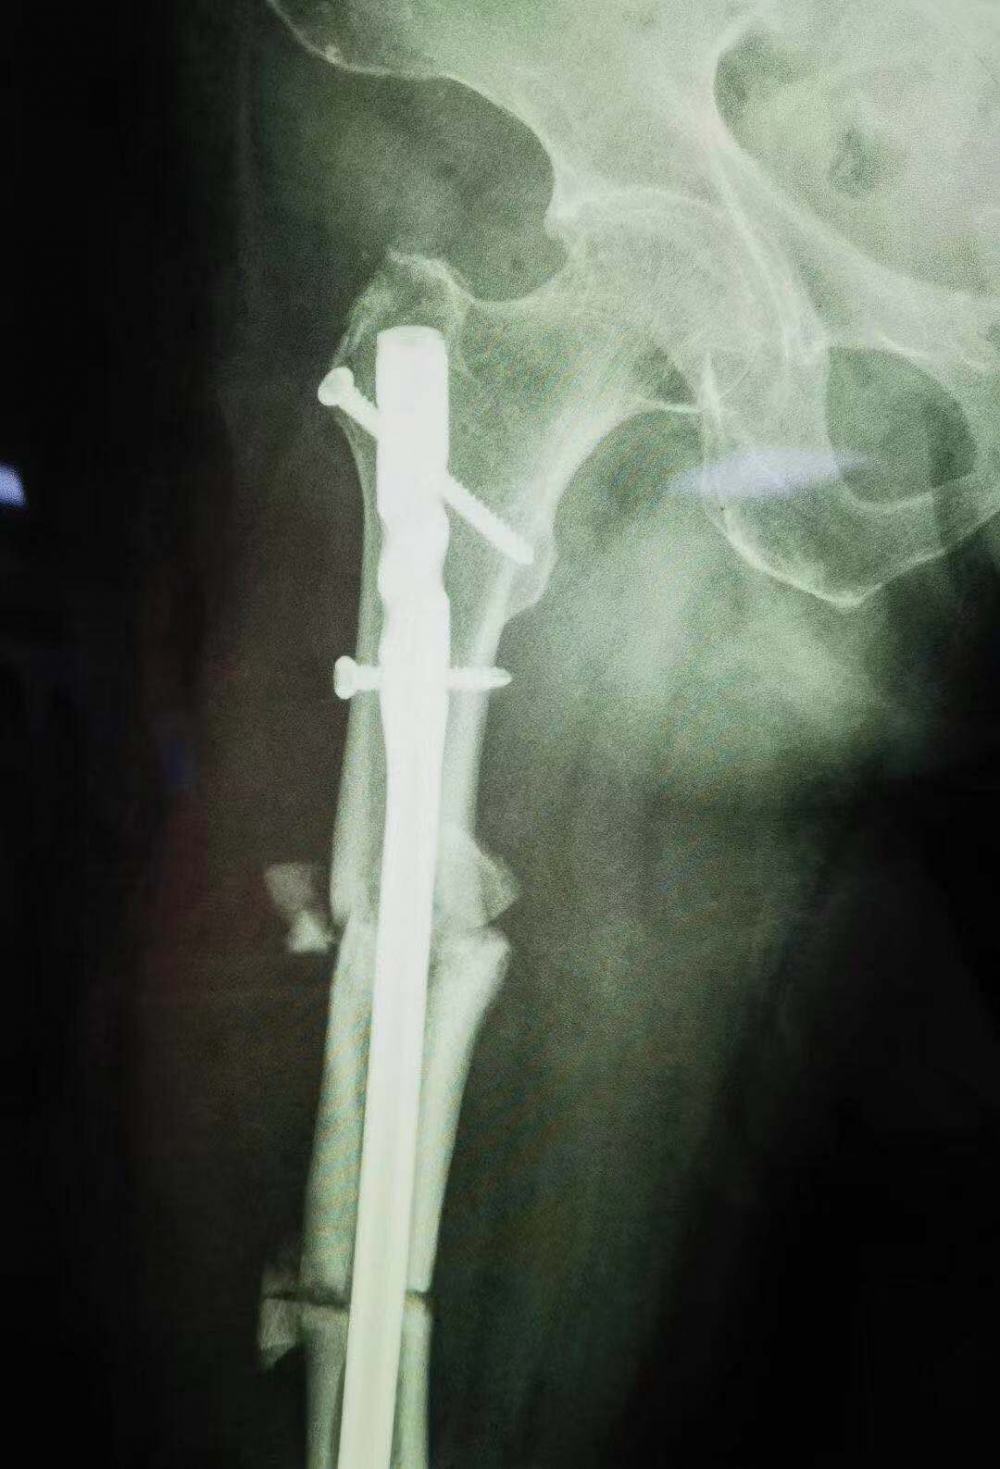

“一箭雙雕”一個手術解決兩次問題

骨傷一科主任汪永泉帶領團隊多次會診,拿出較為可行的三套方案,每套方案進行細致詳盡的評估。最終在取得家屬同意的情況下,確定在7月28日,由骨傷一科主任汪永泉、管床醫(yī)生樊煒聯(lián)合為患者進行手術。

據(jù)汪永泉主任介紹,此次手術很成功,術后通過觀察,病人目前沒有血管的危象,而且整個神經(jīng)沒有牽拉,而且病人整個下肢體長度,也基本達到術前預想的恢復長度。